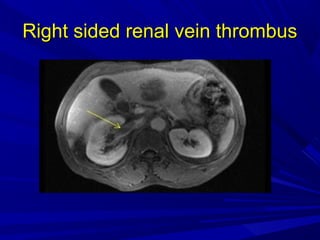

Right sided renal vein thrombusRight sided renal vein thrombus

Right sided renalvein thrombusRight sided renal vein thrombus